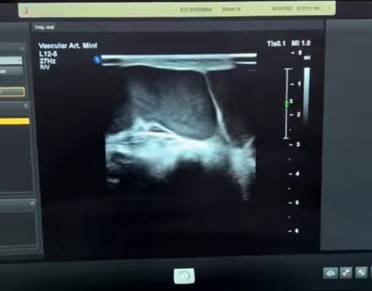

Para su manejo se le realiza bajo anestesia local y eco guiado drenaje percutáneo de contenido hemático a nivel de cara medial y lateral de pierna derecha, procedimiento en el cual se reseca 40 ml, además, inmediatamente se sella la malformación con espuma de polidocanol al 1% en 1:6 ml, complementando esquema terapéutico de especialidad se le envían medias de compresión de 15 – 20 mmHg confeccionada a medida. En cuanto a la evolución, a los 6 días el paciente mejoró los síntomas que motivaron su consulta fundamentalmente la masa y el dolor en cara lateral y medial de pierna derecha Figura D, se complementa con estudio de imagen mediante Eco Doppler modo B transductor lineal, en el cual se observan compartimentos esclerosados, lo que evita el crecimiento de la malformación vascular, además a través de la ecografía realizada, se ratifica los resultados como satisfactorios tanto desde la perspectiva funcional como estética Figura E.

Descripción: Descripción: Descripción: C:\Users\VALE\AppData\Local\Microsoft\Windows\INetCache\Content.Word\61ad1b5f-87a6-4190-bde7-0469daabc23d.jpg

Figura E. Se observa en Eco Doppler modo B región derecha esclerosada.